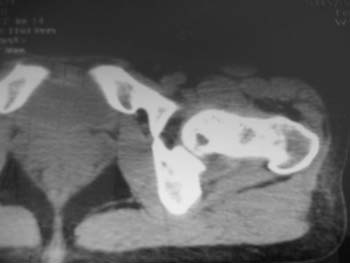

以下是引用358450m在2008-8-12 12:12:00的发言:[br]骨囊肿

以下是引用yangyudong333在2008-8-12 14:30:00的发言:[br]考虑退京变所致关节面下骨质囊变

以下是引用随光逐影在2008-8-12 20:40:00的发言:[br]考虑邻关节骨囊肿或骨内腱鞘囊肿。